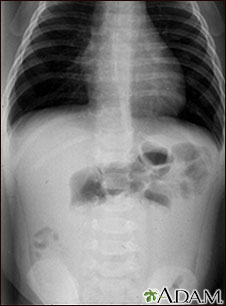

Intussusception - X-ray

This abdominal x-ray shows an intestinal condition in which a loop of bowel has slipped into another section of bowel (intussusception), causing swelling, reduced blood flow, obstruction, and tissue damage. Intussusception requires emergency treatment (barium enema or surgery) to prevent intestinal tissue death (necrosis), intestinal perforation, peritonitis, and death.